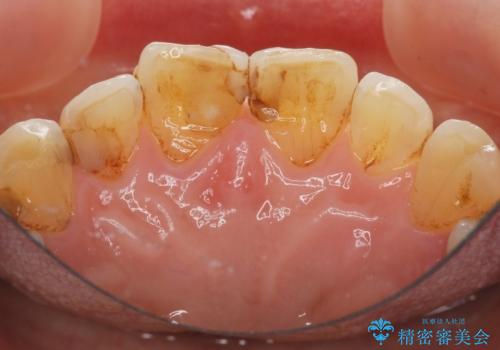

- 前歯の小さな虫歯を複数回治療した結果、つぎはぎだらけになってしまい審美的な改善を求めて来院されました。

これ以上のコンポジットレジン修復は更なる審美障害を招きかねないので、全体を覆うセラミッククラウンを選択します。